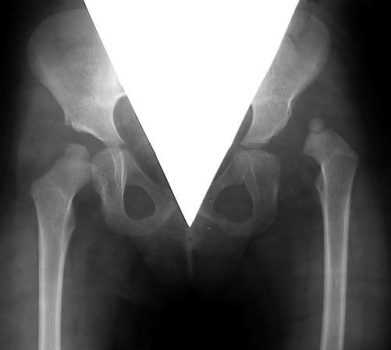

Рентгенограммы больной Т., 10 месяцев. Диагноз: врожденный вывих бедра справа.

- второй тип, с преобладанием бедренного компонента: деформация шейки бедра (антеторсия либо вальгусная деформация — см. рис 1-2); вертлужная впадина поражена незначительно, либо ее развитие нормальное;

Рентгенография обоих тазобедренных суставов с захватом верхней трети обоих бедер на пленке 40/30 см - прямая, с отведением и внутренней ротацией, по Лауэнштейну, 24/30 см - боковые (пораженного сустава, по показаниям или ревизии 40/30 см) с расстояния 1-1,2 м рентгентрубки от кассеты. Рентгенография поясничного отдела позвоночника (2 проекции).